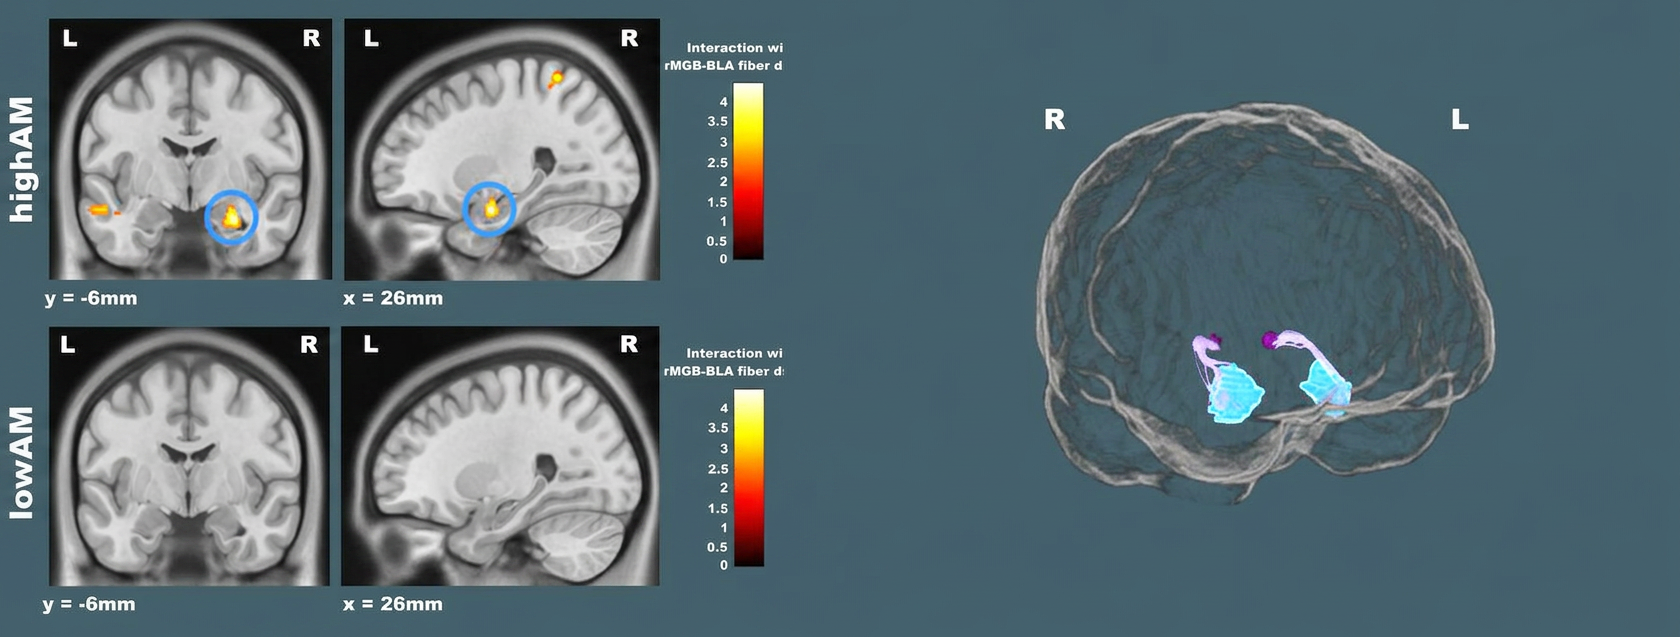

To address these questions, we combine complementary neuroimaging and physiological approaches that allow brain processes to be examined across multiple spatial and temporal scales. We seek to reveal how these subcortical shortcuts may facilitate the detection and evaluation of threatening information. Recent work within the project has begun to provide converging evidence supporting the existence of specialized subcortical connectivity in the human brain. For instance, structural connections linking midbrain auditory centers with the amygdala through thalamic relays appear to resemble circuits previously described in animal models.

These pathways may provide rapid access for emotionally relevant sounds to subcortical affective systems. Importantly, specific properties of these pathways may relate to particular aspects of auditory perception and also to affective processing and individual traits. Ultimately, this project aims to advance our understanding of how the human brain evaluates emotion through phylogenetically ancient subcortical mechanisms, and how these may be involved in conditions related to emotional dysregulation or affective traits.